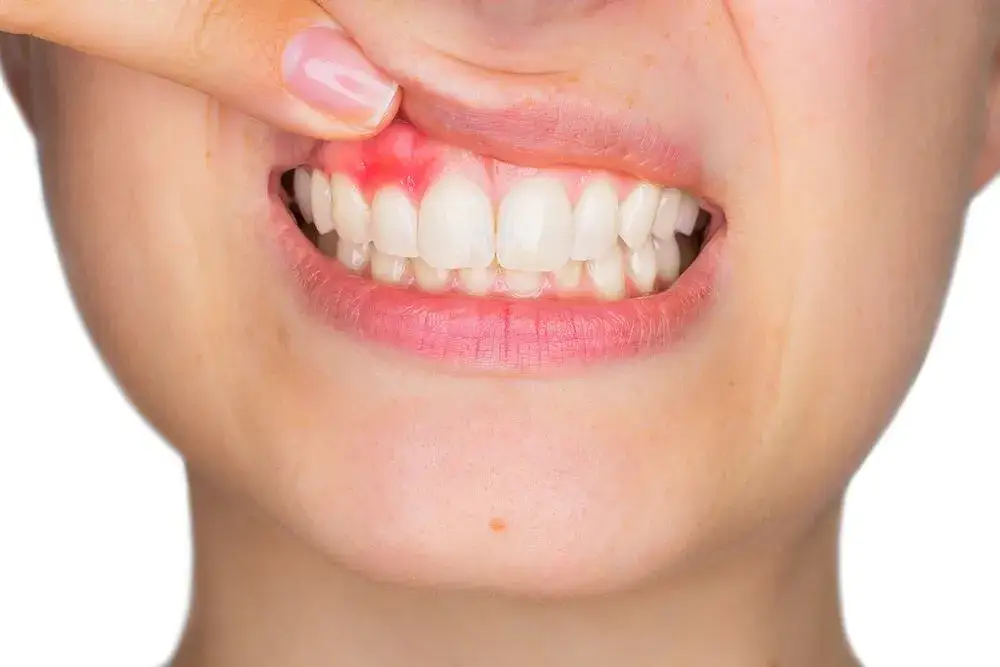

Krwawienie dziąseł podczas szczotkowania lub używania nici dentystycznej to jeden z najbardziej typowych i często pierwszych objawów zapalenia. To taka "czerwona flaga", która mówi nam, że coś jest nie tak. Nie wolno jej lekceważyć, ponieważ świadczy o toczącym się w dziąsłach procesie zapalnym. W zaawansowanych stadiach zapalenia, krwawienie może pojawić się nawet samoistnie, bez żadnego mechanicznego bodźca.

Jak już wspomniałam, krwawienie to kluczowy sygnał. Zwróć uwagę, czy pojawia się ono regularnie podczas codziennej higieny jamy ustnej. Jeśli po umyciu zębów lub użyciu nici dentystycznej na szczoteczce lub w lustrze widzisz ślady krwi, to znak, że Twoje dziąsła są podrażnione i prawdopodobnie objęte stanem zapalnym. Pamiętaj, że zdrowe dziąsła nie krwawią. To fundamentalna zasada, którą warto zapamiętać.

Aby lepiej zobrazować różnicę, przygotowałam porównanie wyglądu zdrowych dziąseł i tych dotkniętych zapaleniem:

| Mają naturalny, bladoróżowy kolor. | Są intensywnie czerwone lub sino-czerwone. |

| Są zwarte i jędrne w dotyku. | Są nabrzmiałe, spuchnięte i często wydają się "rozpulchnione". |

| Nie powodują dyskomfortu ani bólu. | Mogą być bolesne i tkliwe na dotyk. |

Oprócz widocznych zmian, zapalenie dziąseł często manifestuje się poprzez uczucie bólu, tkliwości i ogólnego dyskomfortu. Może to utrudniać codzienne czynności, takie jak jedzenie czy właśnie mycie zębów. Dziąsła stają się wtedy bardzo wrażliwe, a każdy dotyk może wywoływać nieprzyjemne odczucia.